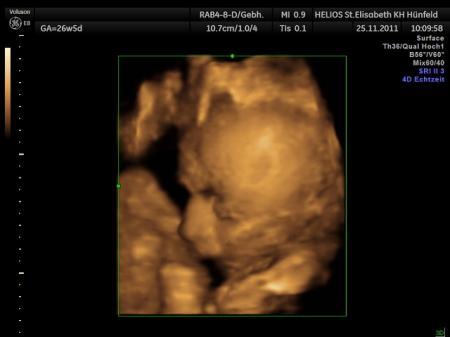

Hallöchen Mädels. Ich war ja heut früh bei meiner FÄ zum 3.screening. Naja CTG ist in Ordnung, nur wollte der kleine eher schlafen, als sich bemerkbar zu machen. Der kleine liegt derzeit in BEL und mit dem Rücken nach vorn. Er schaut sich also grad meine Nieren und Wirbelsäule genauer an. =) Jetzt das unerfreuliche und etwas was mich irgendwie total schockiert und uns beiden total Angst macht. 1. Der Kleine ist bereits 45cm groß. (Papa: 1,75m, Mama: 1,54m) 2. Ich muss morgen zum Doppler, um eine Unterversorgung auszuschließen, da der Kleine zu wenig wiegt. Sein gewicht 1640gr. 3. Wasser in den Beinen 4. fetale Nieren beiderseits hypoton (?) 5. mütterliche Nieren-> rechts hypoton, links: ohne befund Ich hab so Angst das der Kleine nicht genug versorgt wird und eher geholt werden muss. Das er schon so groß ist verwundert mich nicht wirklich. Mein freund kam damals 5wochen zu früh und war schon 50cm groß. Damit haben wir gerechnet. Aber das gewicht.... hab bis jetzt nur gelesen dass das ok sei, aber meine FÄ meint es ist zu wenig!! Noch dazu findet sie meine VW-Plazenta net ok und meinen Mutterkuchen. Ist wohl verkalkt, meint sie. Wirklich erklärt hat sie uns nix weiter. Ich hatte gestern Vormittag gaaannnzzz wenig bräunlichen ausfluss, was ich ihr auch erzählt hab, aber da ist alles ok. Laut US hängt der kleine sogar 2 wochen zurück, aber mein ET bleibt felsenfest stehen. morgen 13Uhr gehts mit meinem schatz zum Doppler. Hoffe das es ihm dann gut geht, weil er vorher zum Zahnarzt muss... Füllung und ein Zahn wird gezogen. *autsch* Als kommentar steht im MuPa beim 3.screening RG 2. Weiß jemand was das bedeutet?? Ich bin verzweifelt und weiß irgendwie net wie ich damit umgehen soll. Hier ist noch rein gar nix fertig. wollte diese woche den Rest holen für den Kleinen. KiZi ist bestellt und wird in 2-4wochen geliefert, Wickelauflage, Hygieneartikel und Co müssen noch geholt werden, was ich diese woche mit machen wollte.... Jetzt müssen wir wohl noch bissl gas geben, das dann alles soweit fertig ist, wenn er vllt geholt werden muss. denn darauf müssen wir uns derzeit einstellen, meint meine FÄ. Es sei denn er dreht sich jetzt nochmal.... Wirklich hoffnung und mut macht die einem ja nicht, aber naja.... Liebe Grüße, Michaela P.S: wieso kann ich mein bauchbild net hochladen? zu groß ist es wirklich nicht!!

hm.... die tabelle beruhigt mich ungemein!! Aber da müsste ich ja auch einen Nierenstau haben, da meine rechte Niere ebenfalls hypoton ist. hm... komisch. Vllt untersuchen die das morgen im KH auch gleich mit, da sie das auch im MuPa eingetragen hat. Meine Ärztin meinte eben nur das er zu wenig wiegen würde für die Größe und die SSW. Aber wenn eure mäuse auch soviel wiegen (in etwa) wie mein Kleiner, dann beruhigt mich das auch noch bissl mehr. Bin gespannt auf morgen. Hab bei google gefunden, dass das wie ein normaler US ist, nur das da eben der Blutfluss kontrolliert wird. Ob auch alle Innereien normal versorgt werden etc.... naja vllt gibts dann morgen zur Entschädigung ein bildchen? wird da auch eins gemacht beim Dopller, je nach dem wie die Mäuse liegen? Heute hat´s net geklappt weil sich der Kleine meinen Nieren zugewandt hat.